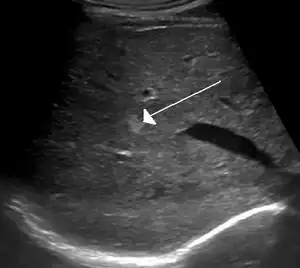

Ultrasound of hemangioma in the liver

On ultrasound, cavernous haemangiomas in liver appeared as homogenous, hyperechoic lesions with posterior acoustic enhancement. On CT or MRI scans, it shows peripheral globular/nodular enhancement in the arterial phase, with portions of attenuation of enhancing areas. In the portal venous phase, it shows progressive centripetal enhancement. In delayed phase, it shows retention of contrast. It shows a high signal on T2 weighted images.[23]